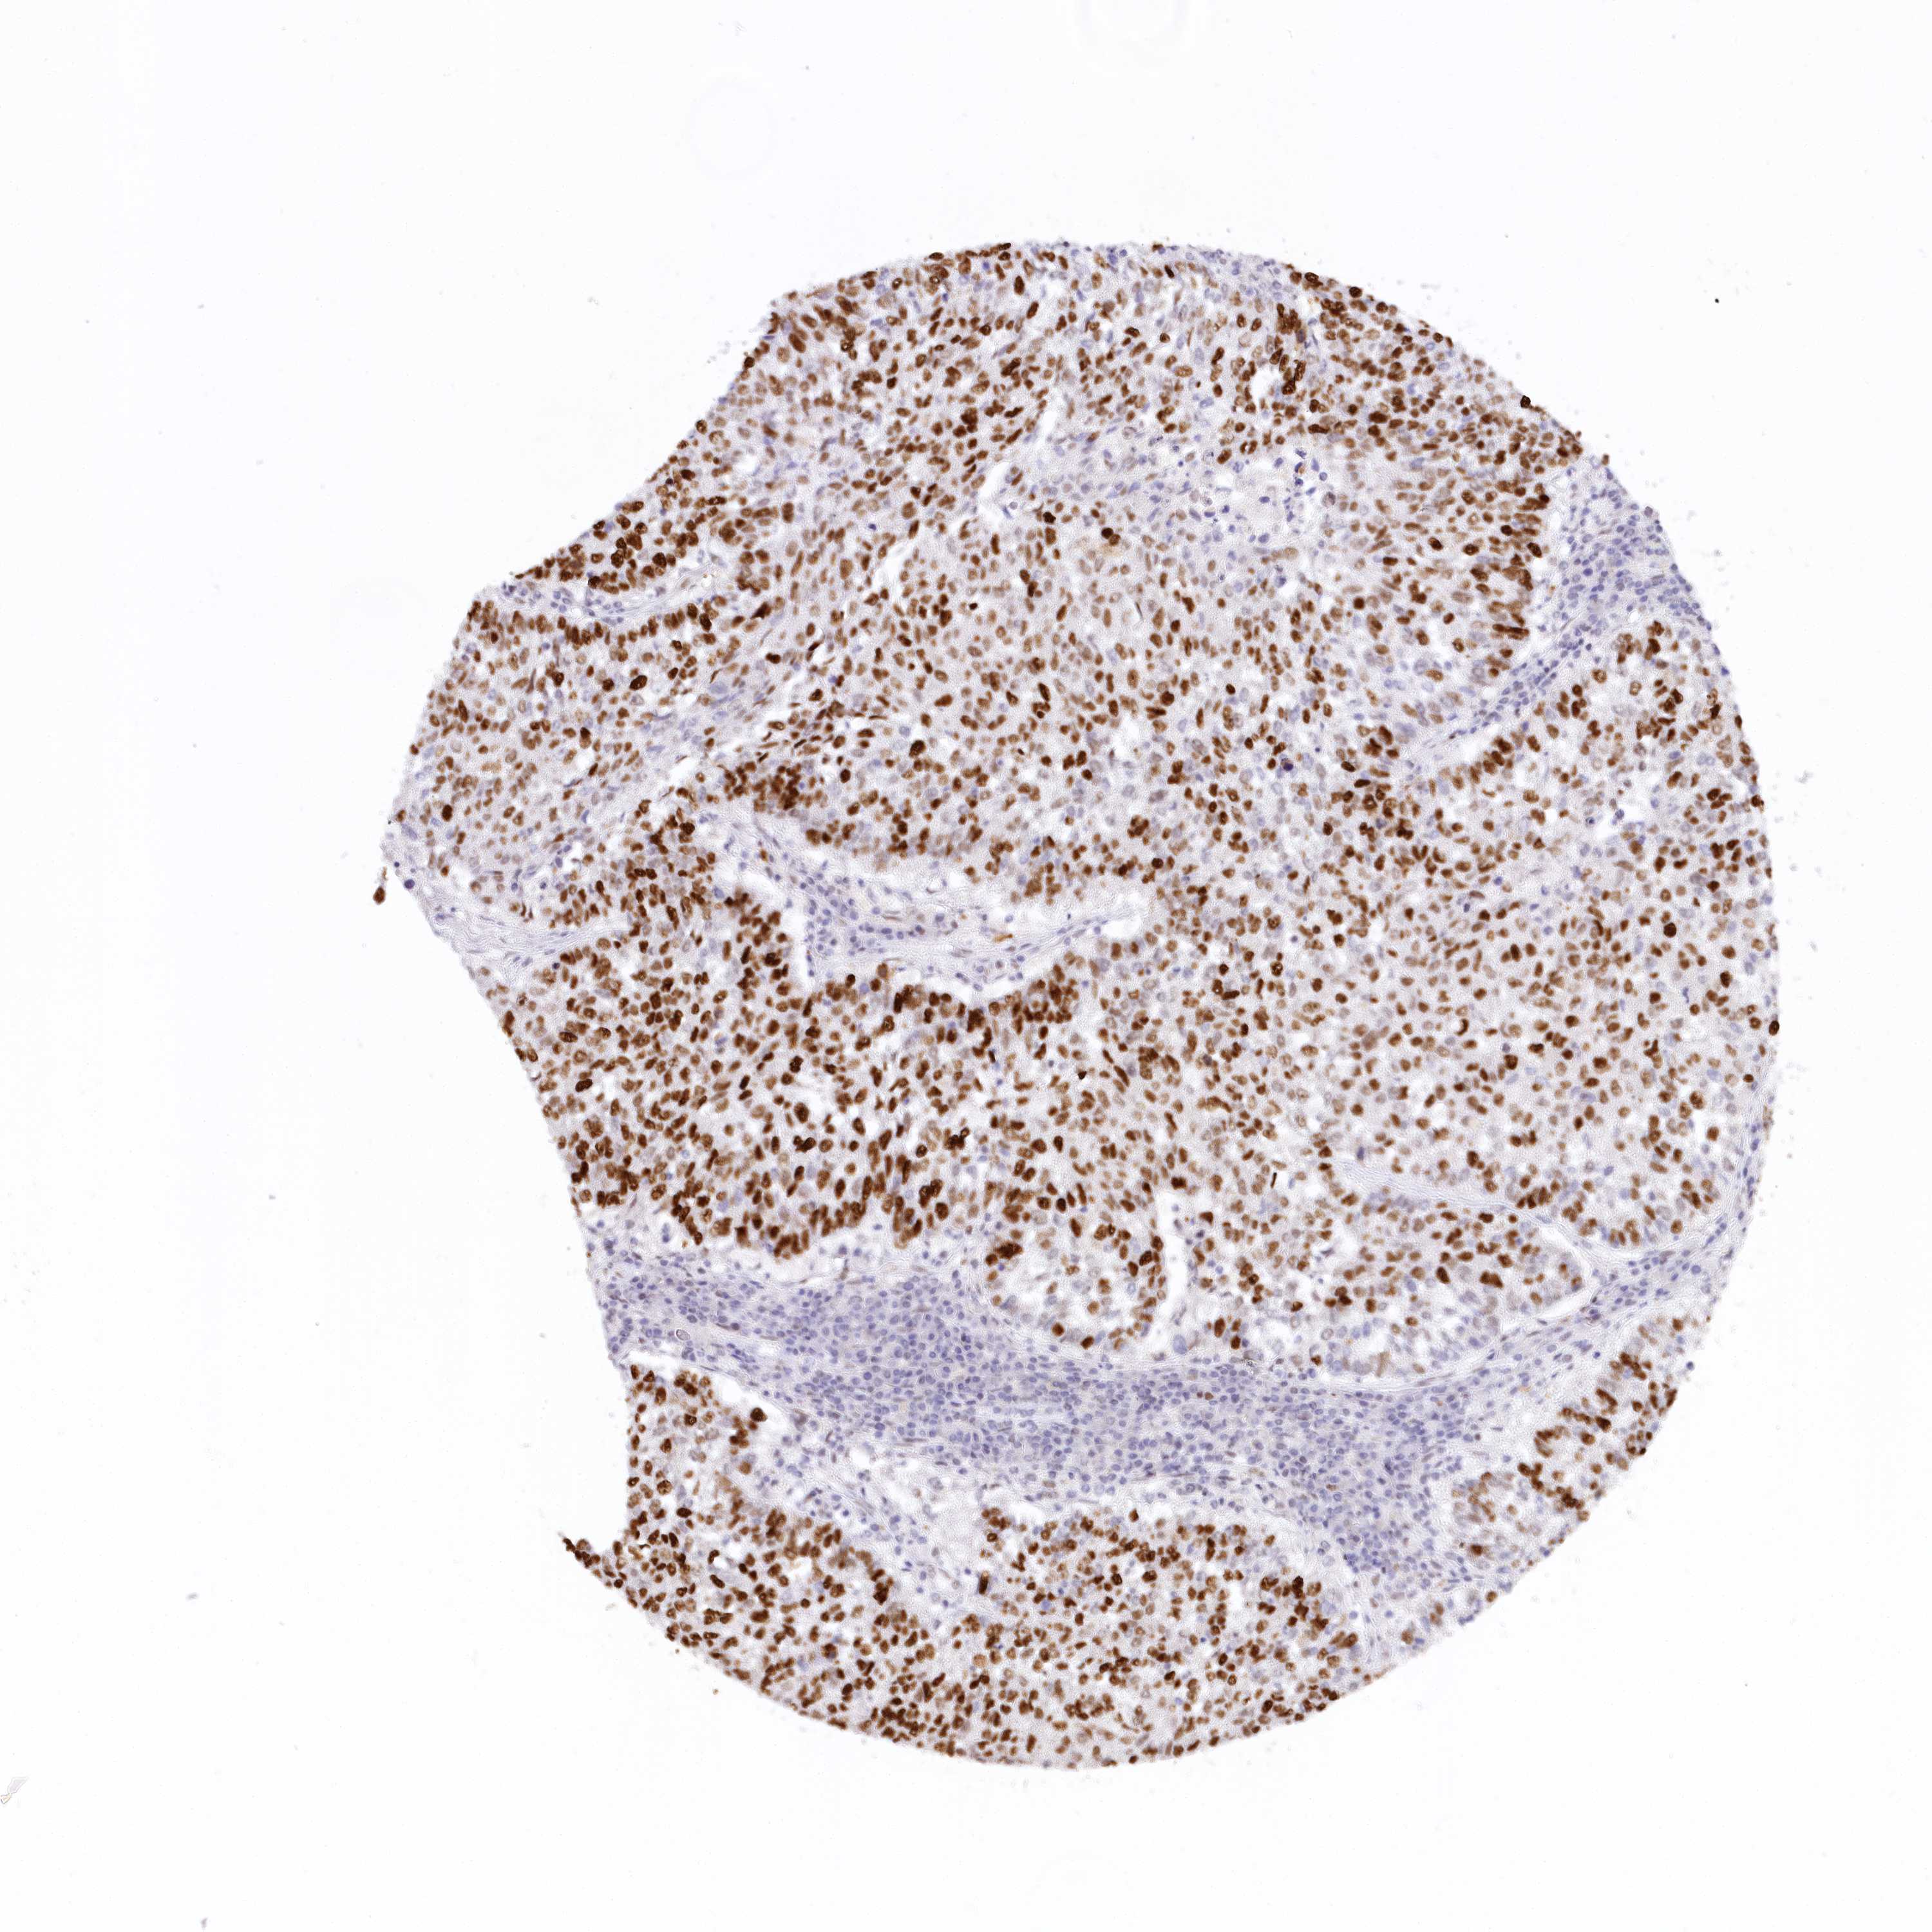

TP53

• CANCER

CANCER LUNG CANCER Show tissue menu

ANTIBODIES